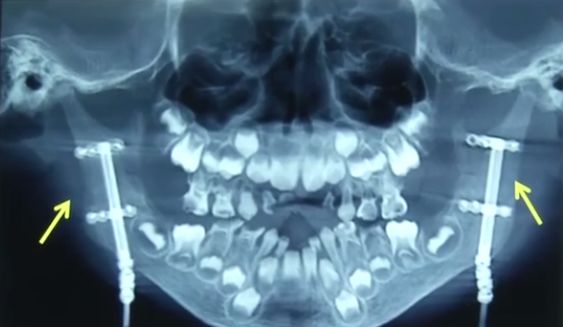

直到前不久,慕女士才带着多多到医院检查,医生检查发现,多多的情况属于比较严重的开颌畸形。

医生提醒,除了先天因素,平时不良习惯的呼吸习惯,也是诱因,简单讲,张嘴呼吸、打呼噜若频繁出现在孩子身上,可能是腺样体和扁桃体肥大引发的。

医生表示,晚上睡觉长期张口呼吸,尤其在两三岁发育高峰期的时候,有可能就会导致颌骨发育畸形,而像多多这样发展成颌面畸形,就很严重了,治疗也有难度。

入院后,多多做了一次手术,院方减免了治疗费,矫正还将继续,医生提醒广大家长,如果孩子出现睡觉打鼾,张嘴呼吸的情况,一定要及时到医院检查,早发现、早干预是最关键的。